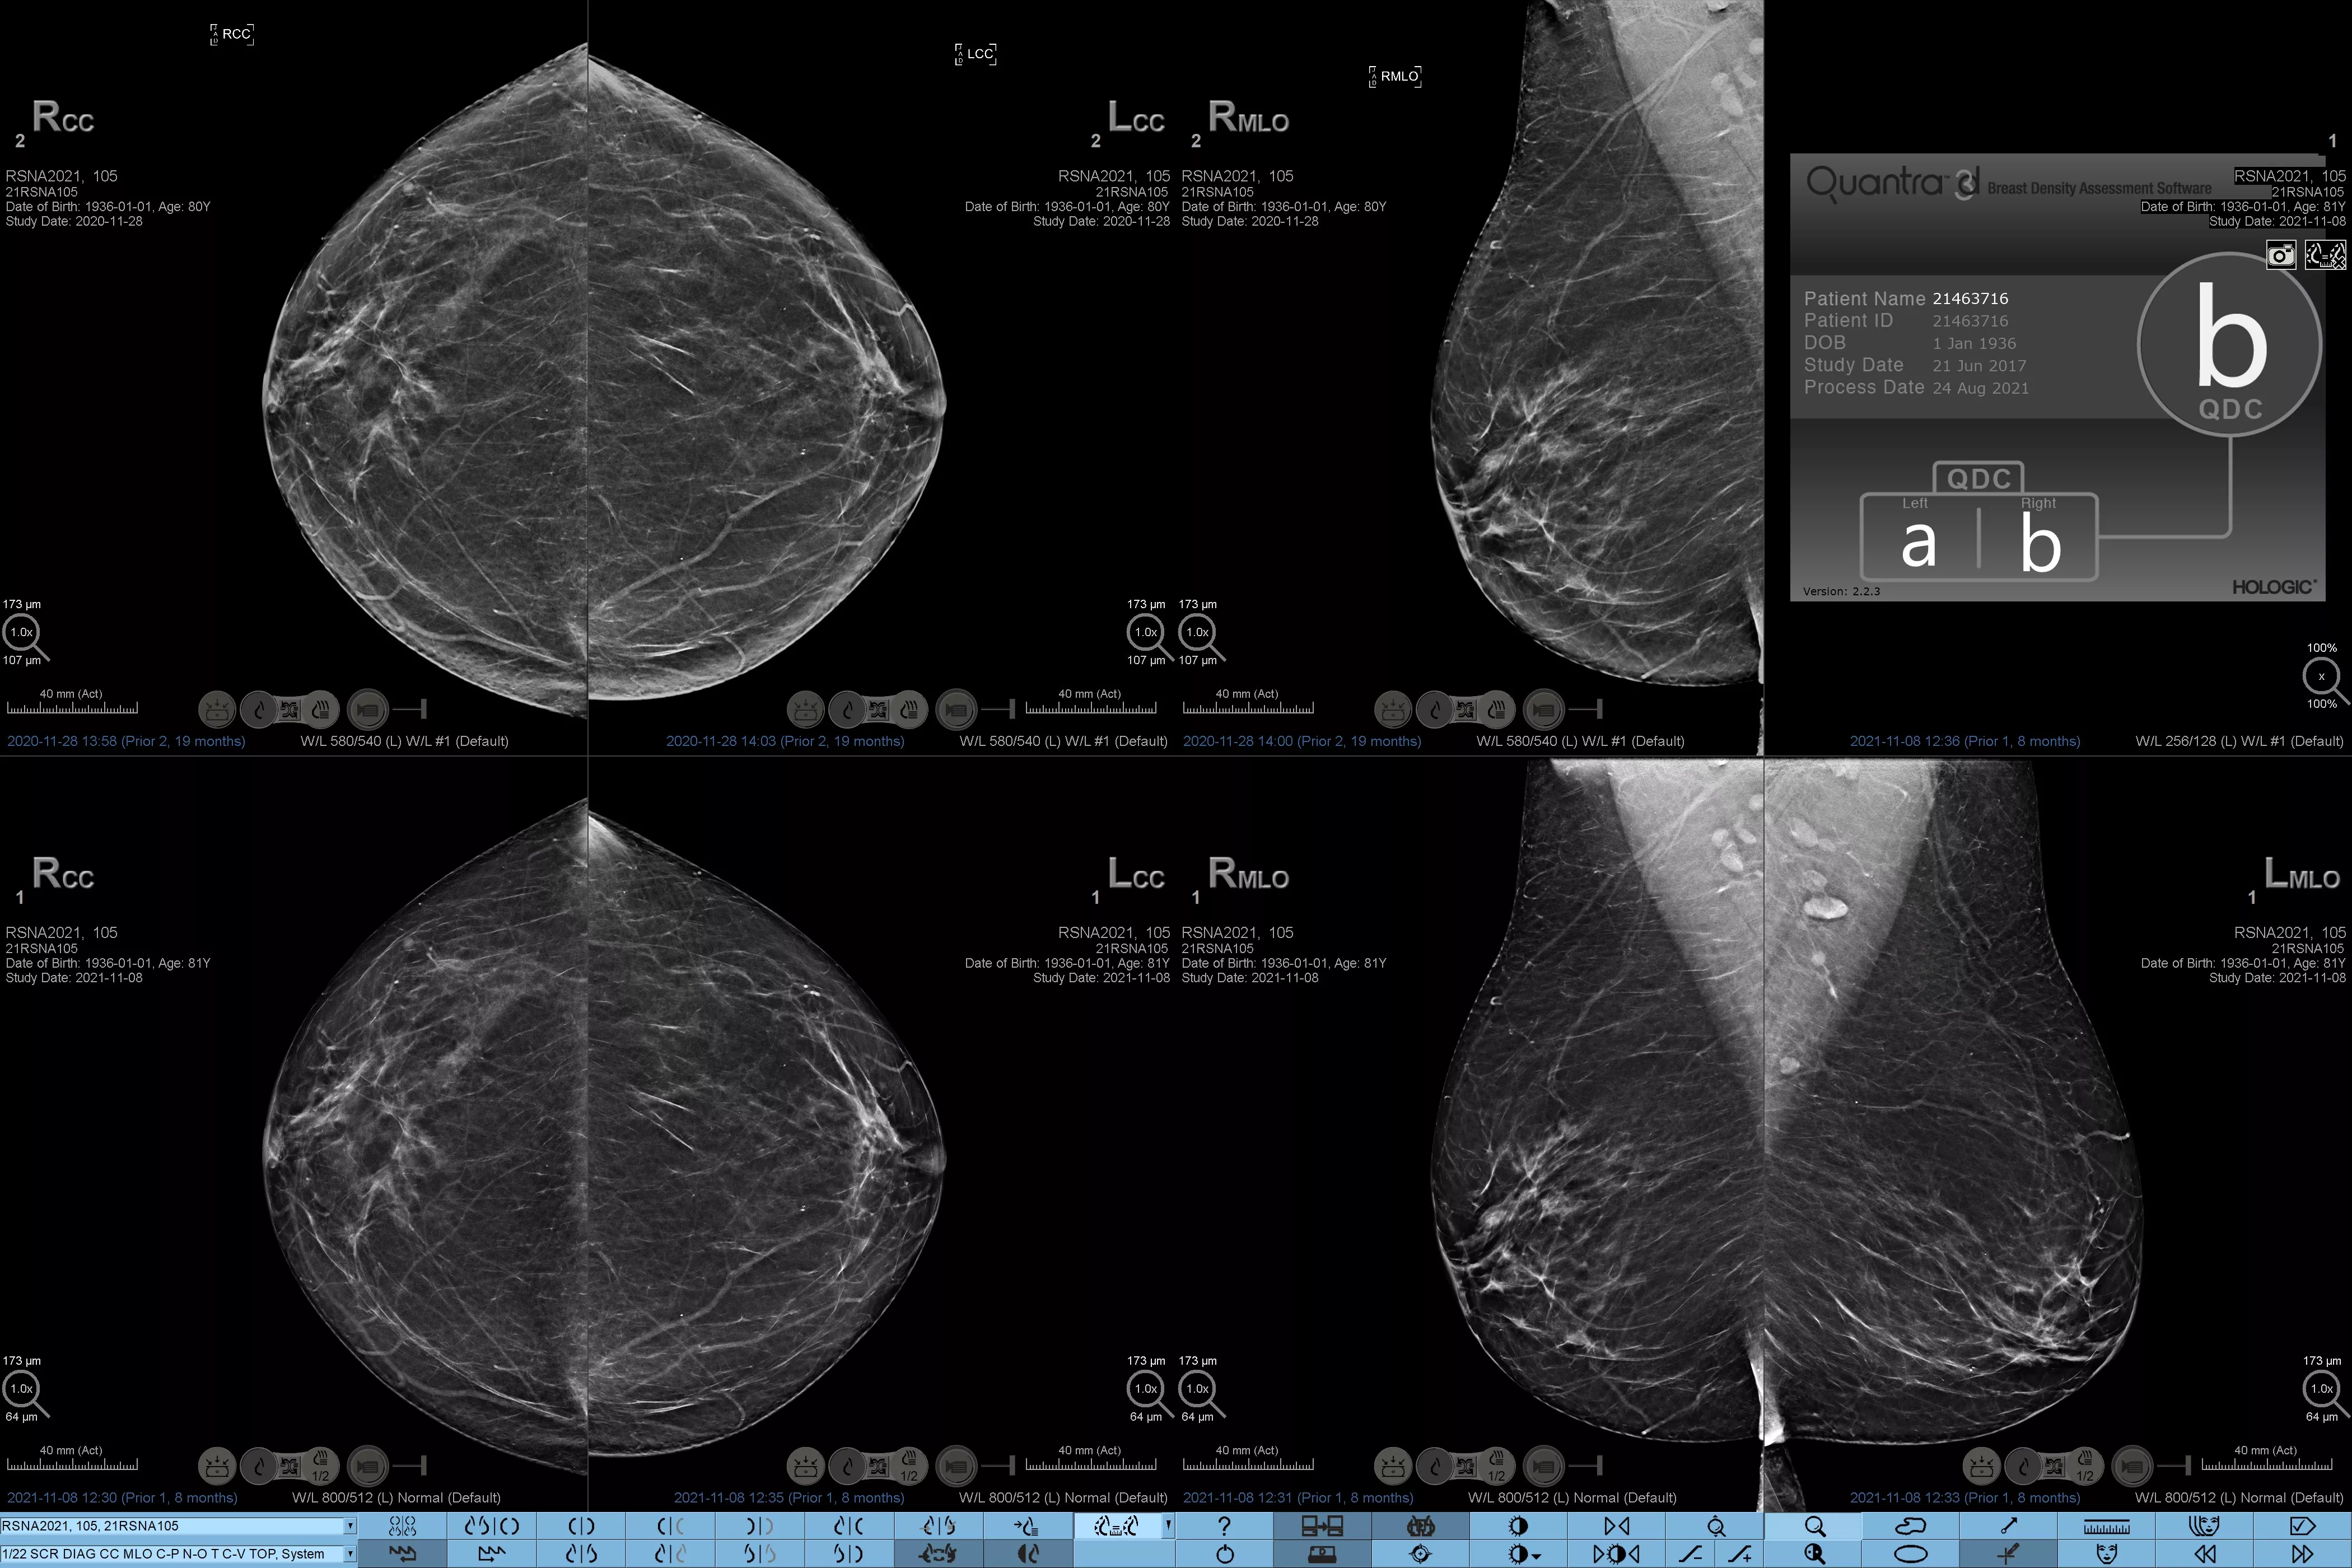

Sabe-se que uma maior densidade mamária aumenta o risco de desenvolver cancro da mama.1 Consequentemente, é fundamental uma análise precisa e não enviesada. O software de tecnologia Quantra, com aprendizagem automática, analisa a distribuição e a textura do tecido parenquimático, tanto através de imagens de 2D™ como de tomossíntese. Este categoriza a mama em quatro categorias de composição da mama, em conformidade com as diretrizes da American College of Radiology (ACR) BI-RADS Atlas 5th Edition.2

Algoritmo de aprendizagem automática objetivo que define a categoria de densidade mamária com base na análise da textura e do padrão do tecido mamário.

*Os resultados baseiam-se nas categorias ACR BI-RADS, em conformidade com as orientações revistas da American College of Radiation (ACR) BI-RADS Atlas 5th Edition. Tal tem em conta o padrão e a textura, comparativamente ao volume, ao determinar a densidade.